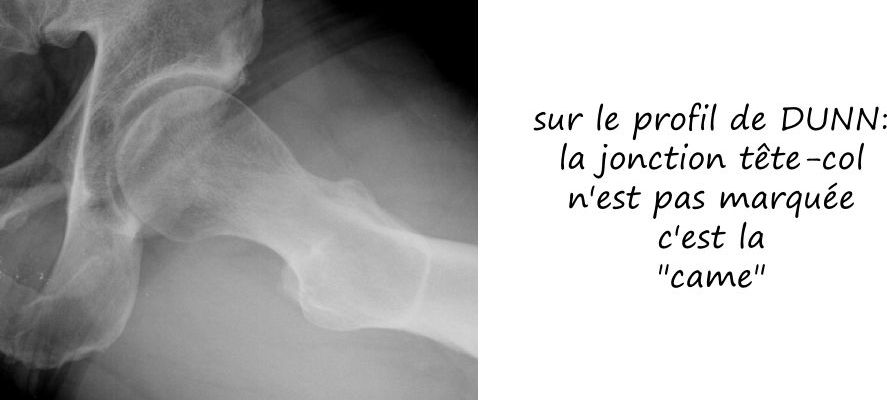

- par effet came: le facteur prédominant est l’excroissance osseuse de la face antérieure du col fémoral

Radiologie standard

Le conflit fémoro acétabulaire se décèle sur de simples radiographies de la hanche, notemment sur le profil de DUNN qui expose la face antérieure du col fémoral. Sur cette radio est estimée l’angle alpha, correpondant à l’angle formé par l’axe du col fémoral et une droite passsant par le centre de la tete fémorale et le point de décrochage de la jonction tete-col, et qui est normalement de l’ordre de 45°; il est augmenté dans les conflits par effet came, comme sur cette radio ci dessous.